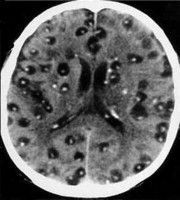

Neurocysticercosis is a preventable parasitic infection caused by larval cysts (enclosed sacs containing the immature stage of a parasite) of the pork tapeworm (Taenia solium). The larval cysts can infect various parts of the body causing a condition known as cysticercosis.